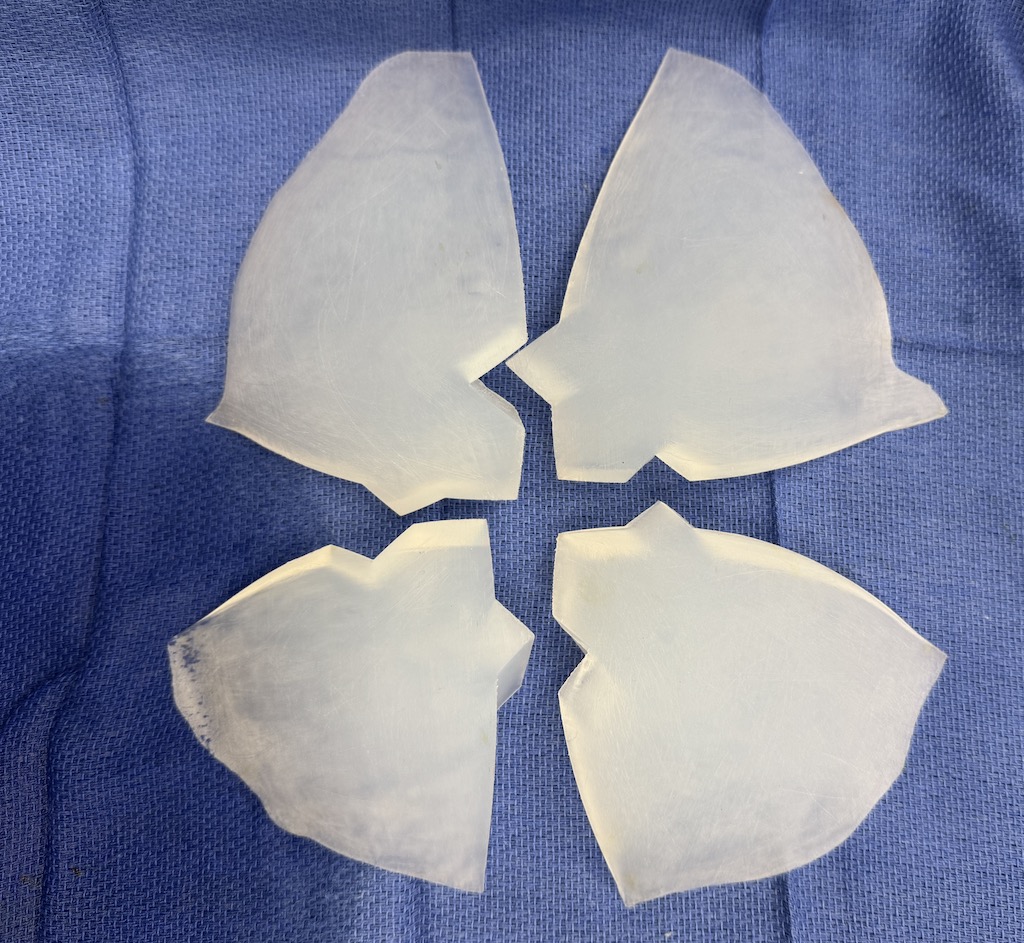

Desire for major head reshaping with a taler and wider head shape.

Placement of large two piece custom skull implant through a sagittal scalp incision.

Desire for major head reshaping with a taler and wider head shape.

Placement of large two piece custom skull implant through a sagittal scalp incision.